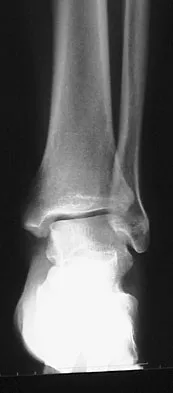

To preserve blood supply to the fractured bone seen in Figures 12a and 12b, care should be taken when exposing which of the following areas?